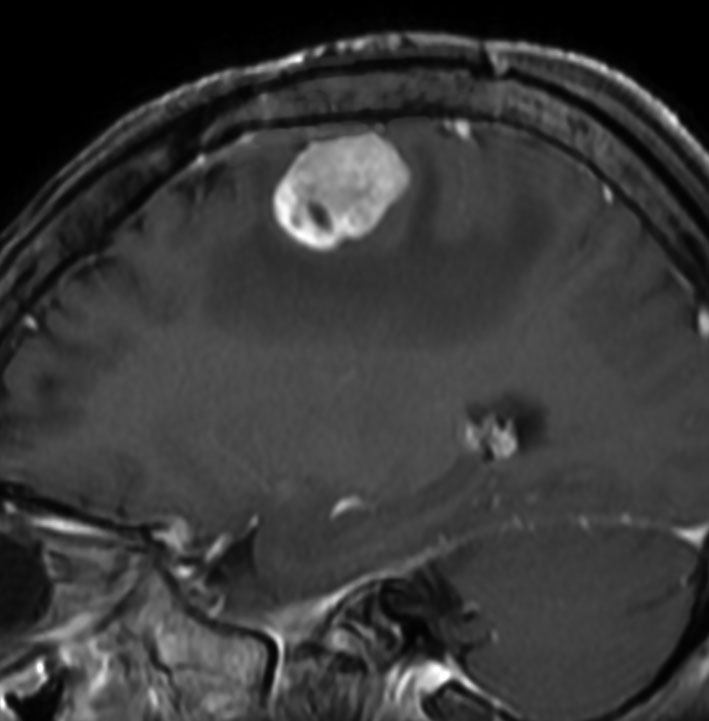

テント上 退形成性上衣腫 グレード3:EPN-ST-RELA negative

膠芽腫を思わせるような,腫瘍内部の壊死,のう胞形成,出血があります。高度の血管増生と動静脈シャントがあり,早期腫瘍静脈描出 early venous fillingがみられます。10代のおそらく右側脳室三角部辺りから発生した退形成性上衣腫です。激しい出血がありましたが全摘出 gross total removal しました。リスクをかえりみない手術も必要です。画像所見も病理組織像も超悪性腫瘍なのですが,治る可能性があるタイプです。